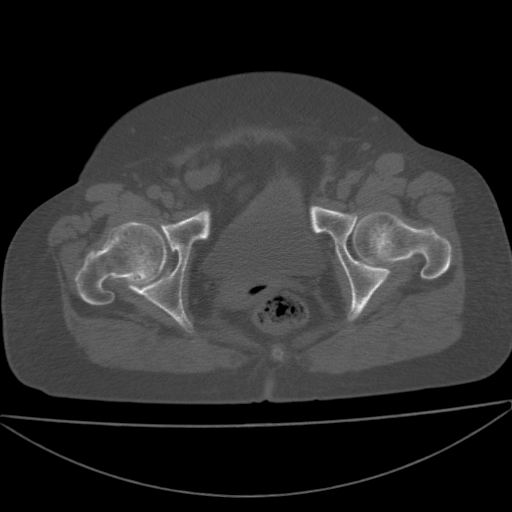

以下是引用余辉在2009-4-23 17:08:00的发言:[br]考虑右髋关节退行性变.股骨颈改变考虑陈旧性骨折可能,股骨头顶部关节面下似有透亮区,股骨头皮质环增厚,考虑有股骨头坏死

以下是引用王显瑞在2009-4-23 16:45:00的发言:[br]考虑股骨颈陈旧性骨折,股骨头缺血型坏死